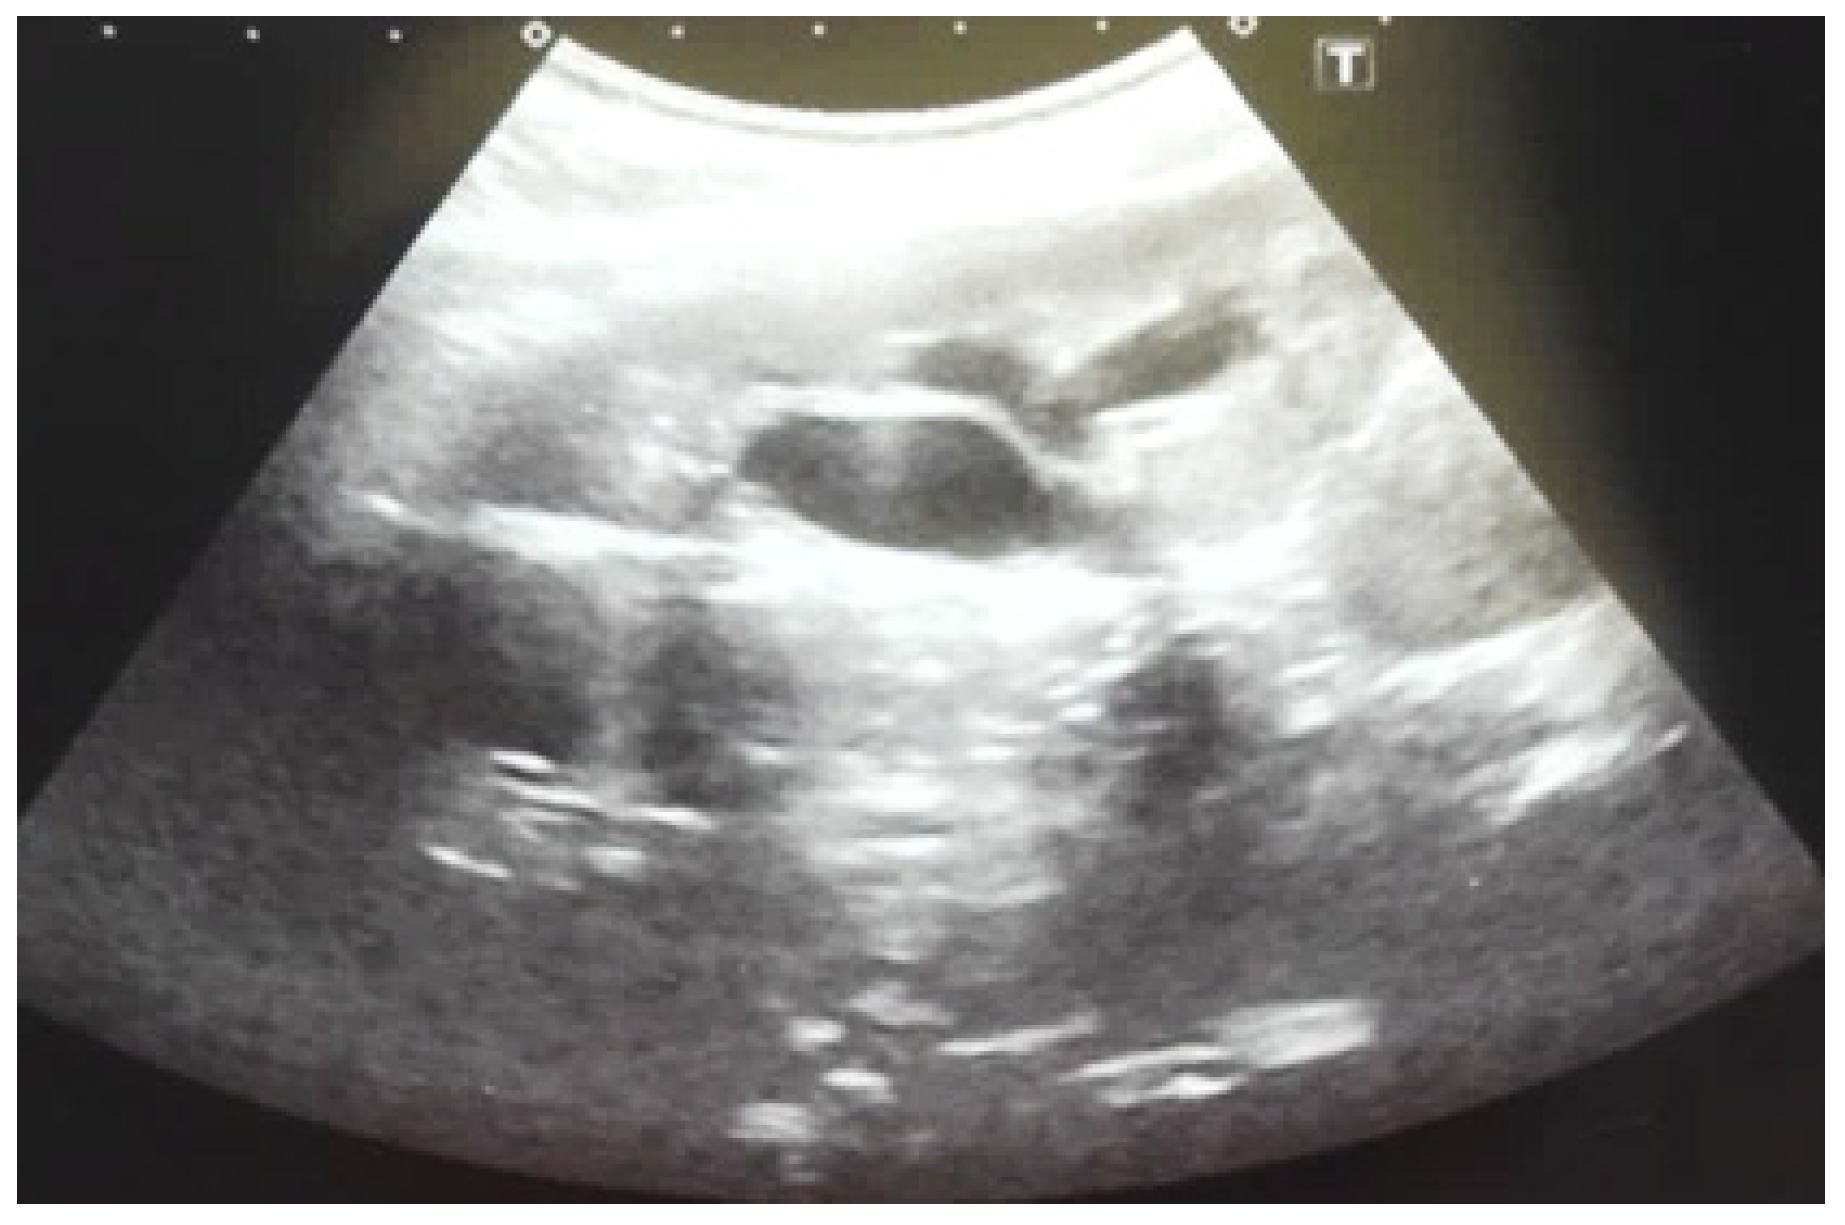

Our experience with congenital malformations of the urinary system refers to the following clinical case (Figure 2, Figure 3, Figure 4, Figure 5, Figure 6, Figure 7, Figure 8 and Figure 9). In the first case, during pregnancy, the 21-week ultrasound determined bilateral renal pyelectasia. The fetus had hydronephrosis on the right; at 31 weeks, it had bilateral hydrocalconephrosis; and at 32 weeks, bilateral pyelectasia. It suffered premature birth at 36 weeks, with complicated anomalies of the forces of contraction, prolonged birth, and birth weight of 2200 g. Postnatal ultrasonography was supplemented by intravenous urography, and bilateral hydronephrosis was determined. Hydrocalconephrosis on the left was discovered. The complete diagnosis was established: congenital renal malformation; bilateral pyelectasia; bilateral hydronephrosis; hydrocalconephrosis on the left; and severe reduced glomerular filtration rate (GFR), GFR > 2SD below mean.

Figure 6. Ultrasound of the postnatal urinary system 10 days after birth. Hydronephrosis on the right.

Figure 7. Postnatal urinary ultrasound. Hydronephrosis on the right (newborn 10 days of age).

Figure 8. Postnatal urinary ultrasound. Hydronephrosis on the left.